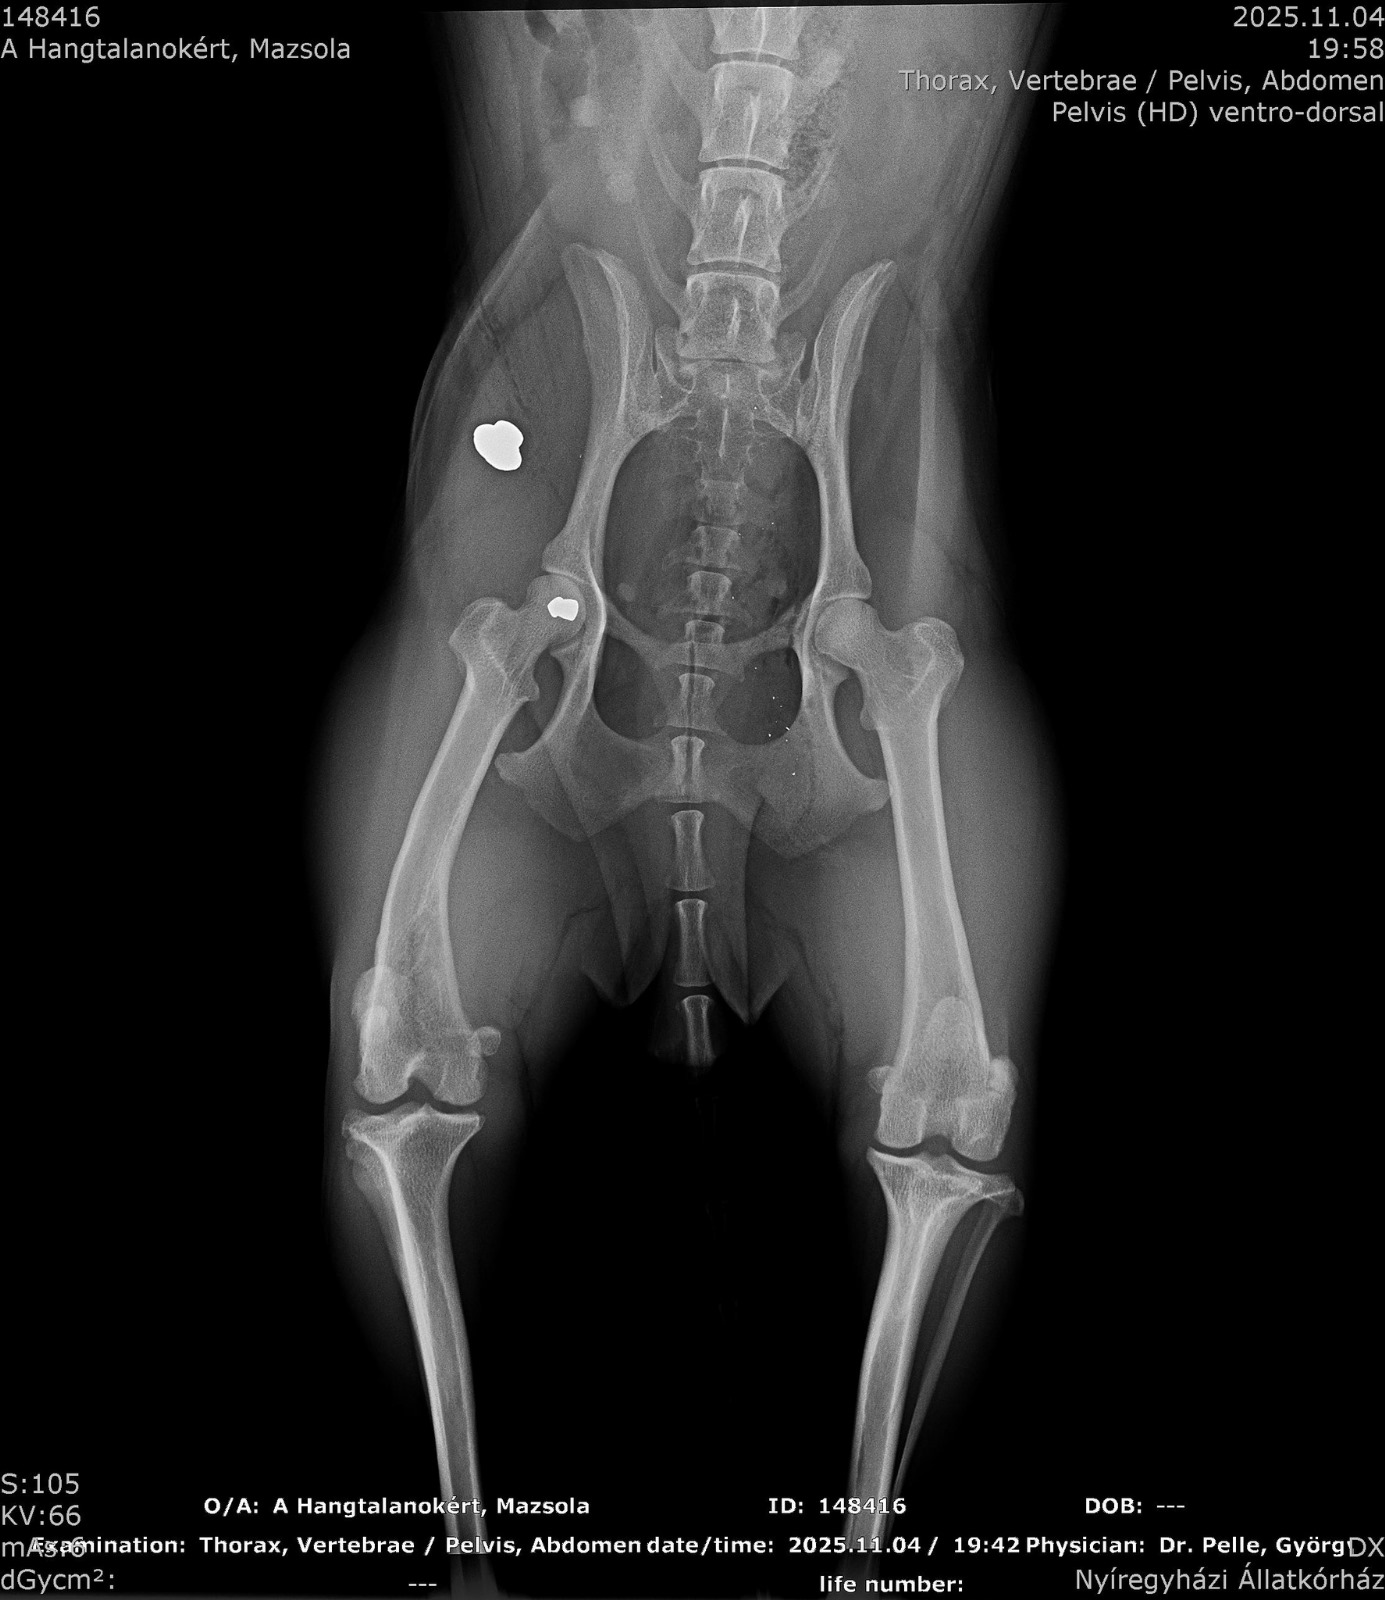

Vorgestern Abend fand ein ungarisches Pärchen eine offensichtlich verletzte Hündin auf der Straße liegend. Sofort war klar, dass sie ihr helfen. Mit dem Verdacht, dass Mazsola (so wurde sie nun getauft) von einem Auto angefahren wurde, ging es in die Tierklinik. Die dortigen Untersuchungen brachten jedoch viel schlimmeres hervor. Auf Mazsola wurde insgesamt 3 mal geschossen! 2 Patronen eines Luftgewehrs steckten in ihrem Körper und die Patrone eines Jagdgewehrs. Ein grausamer Mensch hat die Hündin gezielt verletzt und zum sterben liegen gelassen! Maszolas Zustand war so kritisch, dass sie operiert werden musste. Die dritte Kugel hat ihre Harnröhre, Blase und Gebärmutter durchbohrt… Die Gebärmutter wurde entfernt, die Blase und Harnröhre vernäht. Mazsolas Zustand ist äußerst schlecht und zum jetzigen Stand ist unklar, ob die Hündin überleben wird. Wir hoffen sehr, dass Mazsola große Schutzengel hat und ihr Kämpferwille ungebrochen bleibt!